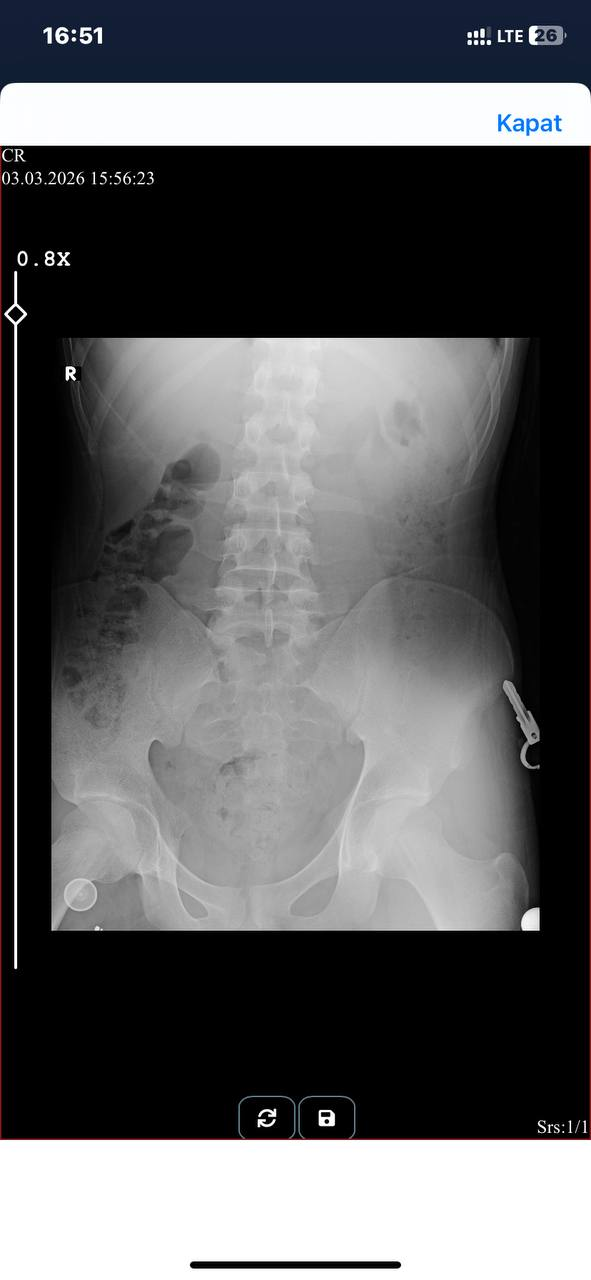

- 03-03-2026, 16:54:29Selamlar az önce idrarda yanma şikayetim üzerine röntgen çektirdim idrar testi polikinlik saati dışında kaldığı için yarın gitmem gerekecek. görüntüye baktım birkaç leke gördüm idrar tahlilinde idrarda az miktarda kan olduğunu söylemişlerdi yarına kadar da bunu stres etmek istemiyorum acaba röntgendeki görüntüler kan mı? yoksa başka birşey mi? bilen hocalarımdan destek rica ediyorum

- 03-03-2026, 17:00:56taş veya kumluk hiçbir ağrı hissetmiyorum karnımda böbreklerimde v.b hiçbiryerimde ağrım yok sadece idrardan hemen sonra 5 dakika kadar süren yoğun yanma varkozmikkreatif adlı üyeden alıntı: mesajı görüntüle